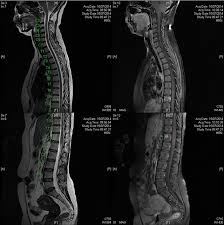

Can Lung Cancer Be Mistaken For Sarcoidosis - Case Report Pulmonary And Liver Sarcoidosis F1000research - Researchers emphasize that clinicians should be aware of systemic sarcoidosis because it can easily be mistaken for cancer progression.. Therefore we suggest that no lesion should be missed in these patients without biopsy by assuming lung involvement of sarcoidosis. Lung cancer should be excluded to confirm a diagnosis of sarcoidosis 4 , although the concurrence of sarcoidosis and lung cancer has been reported 5, 6, 7, 8 . Sarcoidosis patients may be misdiagnosed with tuberculosis, lymphoma, or lung cancer 4 . The standardized mortality rate for lung cancer was 3.26 (5.56 for males and 3.03 for females), indicating that sarcoidosis could be a risk factor for lung cancer. Various organs can be affected including the skin, lymph nodes, and liver.

When sarcoidosis affects the lungs, symptoms can mimic idiopathic pulmonary fibrosis including shortness of breath and a dry cough. Because both mesothelioma and sarcoidosis are hard to detect and present generalized chest and respiratory symptoms, the two conditions can be mistaken for one another. By definition, sarcoidosis is a systemic disease, affecting multiple organs in the body. If it is sarcoid, then you can get the help you need for this condition. There are currently no formal recommendations to guide the differential diagnosis workup between the evolution of lymphoma or a solid cancer and a granulomatous reaction associated with neoplasia. Since sarcoidosis and lung cancer can be present concurrently, performing biopsy to obtain pathology results from any suspected lung lesion in a patient diagnosed with sarcoidosis is essential. What every physician needs to know. Sarcoidosis is known to be a cancer mimicking and masking condition, it can follow cancer or develop concurrently with cancer, and significantly increased risk of cancer can affect sufferers of sarcoidosis.

Pancreatic cancer may also be misdiagnosed as gallstones or pancreatitis, or the inflammation of the pancreas. After some conversations and research i now know sarcoidosis can be mistaken for cancer. A condition called sarcoidosis, most commonly found in the lungs, can be mistaken for cancer, tuberculosis, or other infections, as its symptoms are similar. I've been going to support groups for the disease for 20 years now and find 3 or 4 patients a year who are diagnosed initially as having lung cancer. That same fungal infection is often frequently mistaken for squamous cell carcinoma, or skin cancer, when it shows up on the skin. Sarcoidosis can also affect calcium metabolism, the nervous system, the liver and spleen, muscles, bones and joints, the kidneys, lymph nodes, or any other organ. Various organs can be affected including the skin, lymph nodes, and liver. Sarcoidosis and neoplasia, especially lymphoma, can show overlapping presentations, thus making the diagnosis and treatment harder to deal with. Copd is a term used for a group of obstructive lung diseases. There are currently no formal recommendations to guide the differential diagnosis workup between the evolution of lymphoma or a solid cancer and a granulomatous reaction associated with neoplasia. Since sarcoidosis and lung cancer can be present concurrently, performing biopsy to obtain pathology results from any suspected lung lesion in a patient diagnosed with sarcoidosis is essential. Despite careful preparation, it thus remains difficult to distinguish between these conditions even when lymph nodes are strictly evaluated. Only 10 similar cases had been reported previously.